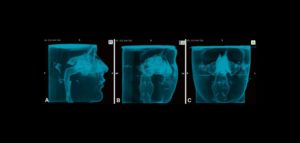

158 – Uso intraoperatorio de la CBCT para la identificación y localización de canales calcificados

Se sabe que la tomografía computarizada de haz cónico (CBCT) produce exploraciones tridimensionales de la dentición, las estructuras duras maxilofaciales y la relación de las